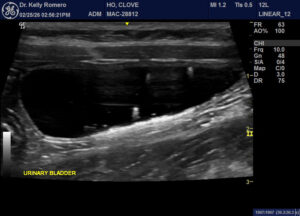

3 yr FS DSH with persistent urinary incontinence. Urinalysis x 3 reported hematuria, mild number of WBCs, no bacteria or crystals and good concentration. One urine culture performed was negative. Pet has been on Clavamox and Zenequin previously. The only medication that seems to make a significant difference is gabapentin but owner is concerned about long term safety. Suspect this is idiopathic cystitis, but please comment on the urinary bladder. Are these just crystals with some shadowing vs. very small uroliths vs. gas?

There is both floating and dependent hyperechogenic sediment – most likely dealing with idiopathic/interstitial cystitis.

If not already on put onto a urinary-type diet such as Hills CD-stress. Gabapentin is controlling the pain associated with the cystitis and try and get the dose to the minimum effective dose. Environmental enrichment can also help in these cases.